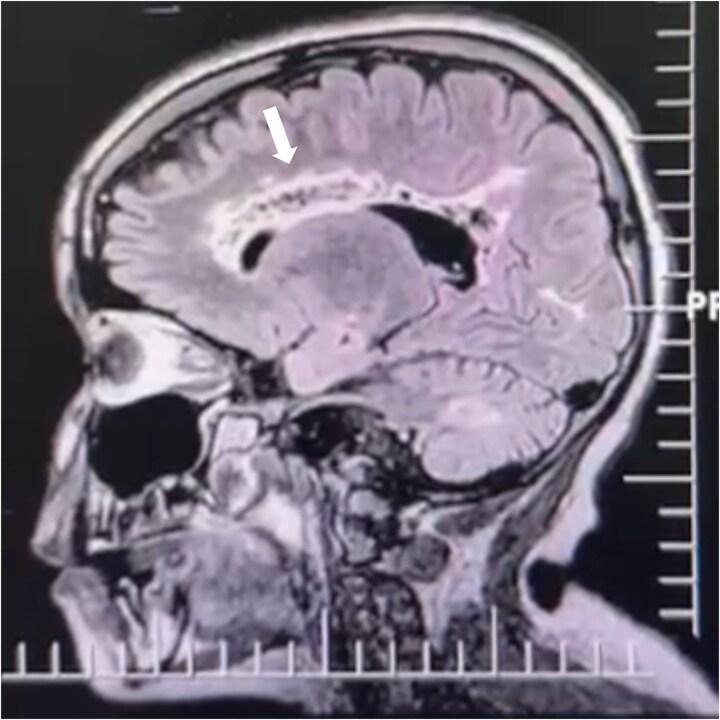

Dandy-Walker syndrome (D-WS) is a rare congenital brain anomaly that primarily impacts the fourth ventricle and cerebellum. Its variant is even rarer and includes cerebellar dysgenesis, with possible posterior fossa enlargement and variable cerebellar vermis hypoplasia.

丹迪-沃克综合征(D-WS)是一种罕见的先天性脑畸形,主要影响第四脑室和小脑。其变异型更为罕见,包括小脑发育不全,可能伴有后颅窝扩大和小脑蚓部发育不全程度不一。